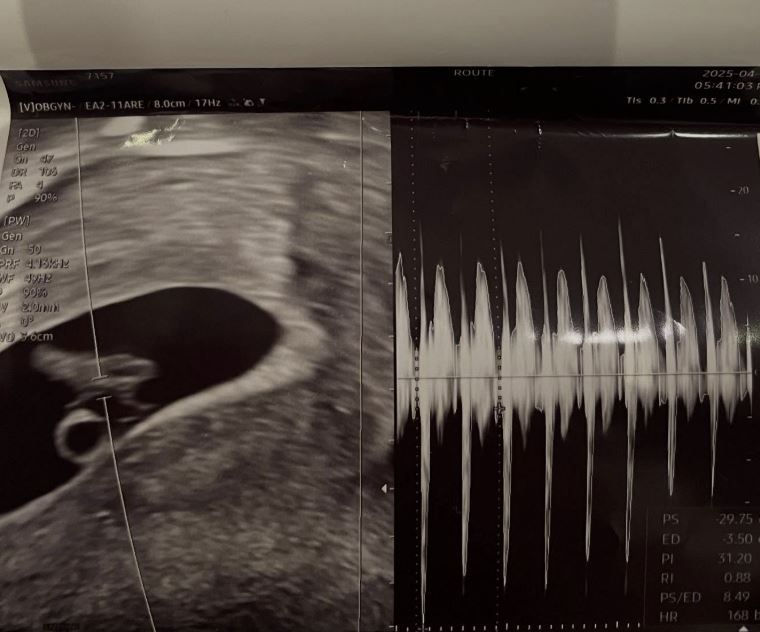

서민재는 2일 자신의 개인 채널에 "아빠된 거 축하해"라는 글과 함께 여러 장의 사진을 업로드했다. 남자친구와의 데이트 사진과 더불어 임신을 알리는 초음파 사진을 공개한 것.